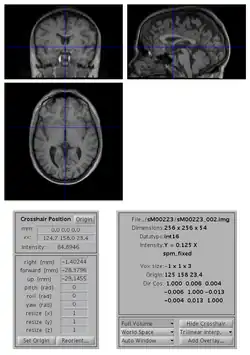

- open the image with SPM Display

- move the crosshair position so that it roughly points to the anterior commissure (AC).

- click on the Set Origin button

- click on the Reorient button and press done (your image is already selected). If you want to apply the same transformation to other images (e.g. if you have a series of functional images), select them all at this stage.

- say No to Do you want to save the reorientation matrix?

This will set the origin of the image (0 0 0 mm coordinates) to AC. You might also want to rotate the image such that it is better aligned with MNI space: to do so, you also need to edit the entries for the rotations (in radian) along the pitch, roll and yaw axes.